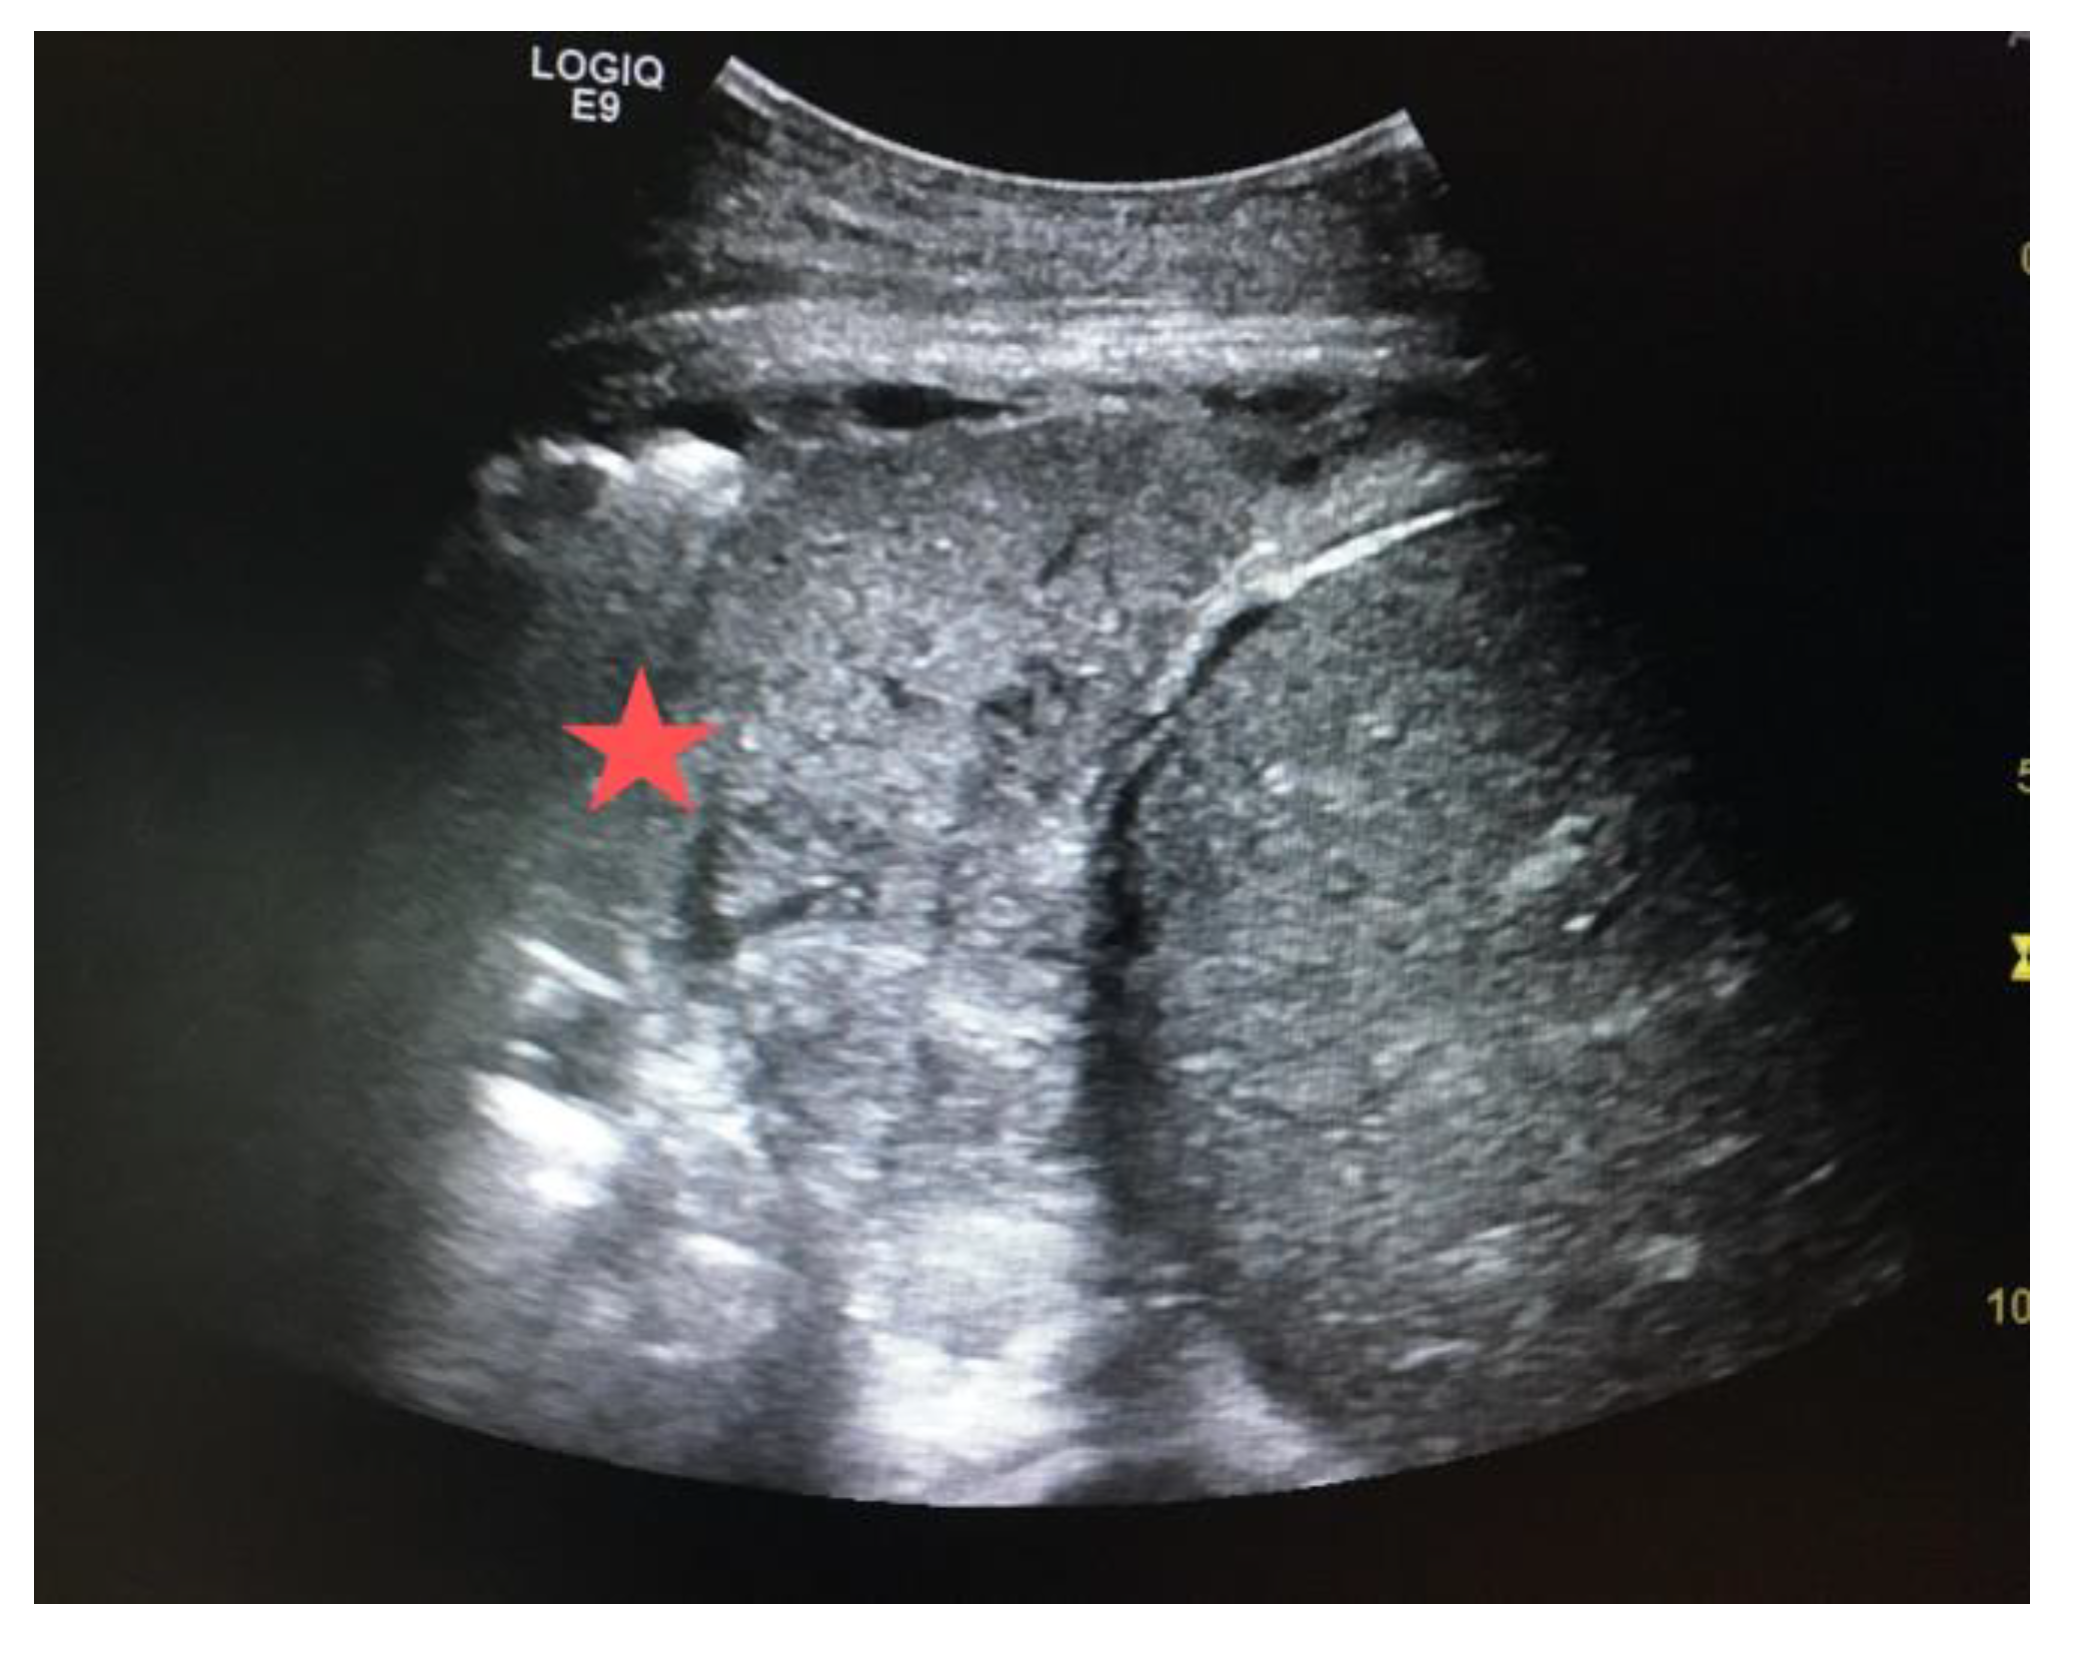

Hypoxia, frequently accompanied by elevated carbon dioxide levels (hypercarbia) resulting from respiratory conditions, accounts for the majority of noncardiac arrest cases. Cardiac arrest solely due to hypoxemia is infrequent. Pulseless electrical activity (PEA) commonly entails complete airway obstruction and typically manifests within 5–10 min. The underlying factors leading to hypoxia, like pleural effusion or consolidation, can be identified through use of sonography once airway control has been established. Sonography excels at distinguishing pleural effusions by detecting even small amounts: as low as 3–5 mL. In pleural effusion, fluid localizes superior to the hemidiaphragm (Figure 8). As regards to consolidation, it typically presents as a hyperechoic area with air bronchograms, often associated with a loss of normal pleural-line dynamics. A specific sign, a shredded pattern, can be seen. It appears as irregular, fragmented lines resembling shredded paper. This pattern can also become tissue like; the complete loss of aeration permits the transmission of ultrasounds through various structures, rendering bronchi and pulmonary vessels visible (Figure 9).

Figure 8.

Large volume anechoic effusion visualized superior to the diaphragm and spleen on a bedside ultrasound image.